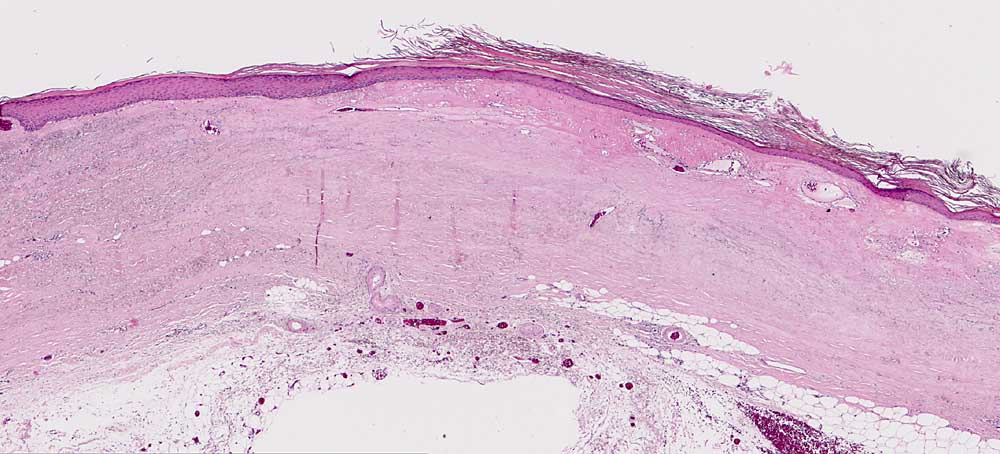

AP/ Chronische Radiodermatitis

Chronische Radiodermatitis

Therapiefolgen

Haut

Haut, Rumpf

Normalbefund